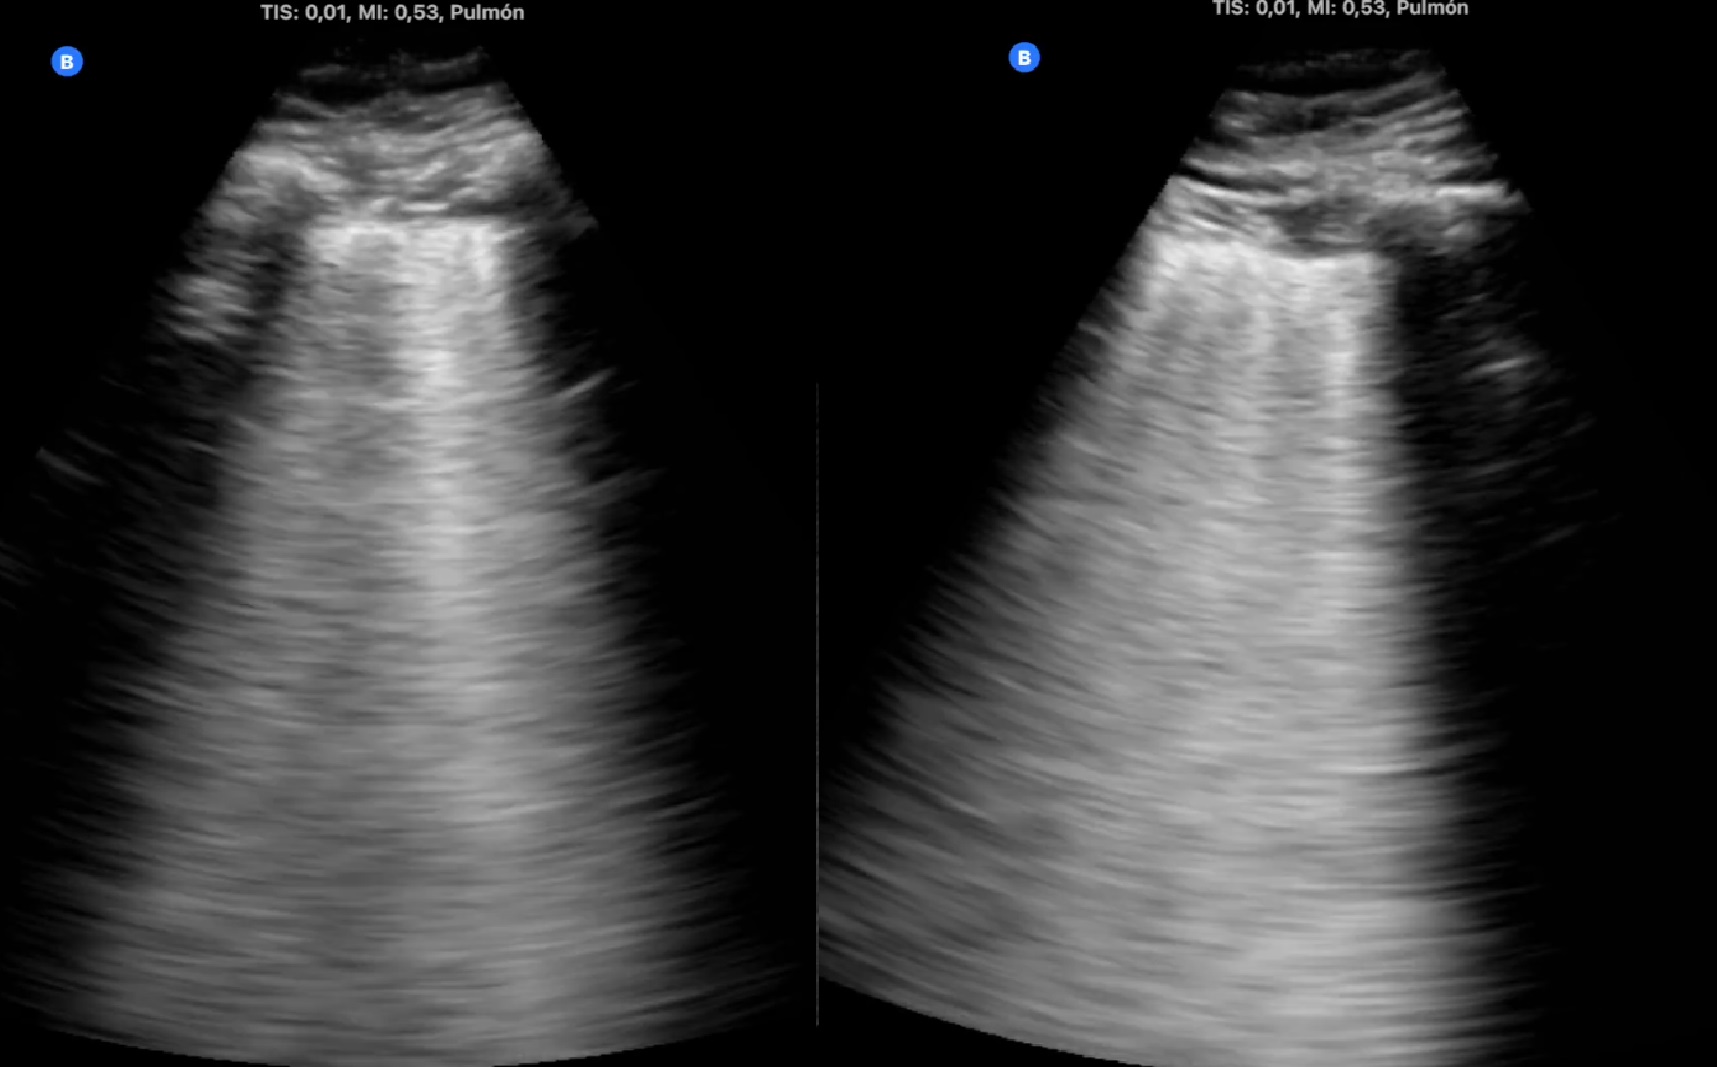

2. Consolidación de mayor tamaño (figura 2), con zonas de pulmón blanco y líneas B confluentes adyacentes a la misma (figura 3), en zona anterior y lateral derechas. Se vuelve a auscultar apreciando sólo leve disminución de murmullo vesicular en la zona.

Desaparición de síntomas en los primeros dos días. Seguimiento ecográfico que muestra la desaparición de la neumonía a los 15 días en el primer caso y reducción paulatina del tamaño de la lesión en el segundo.